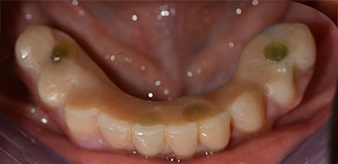

Im Anschluss erfolgt die Abformung und Bissnahme, sodass die Zahntechniker umgehend mit der Anfertigung der provisorischen Arbeit beginnen können. Diese wird im Anschluss am gleichen Tag eingeschraubt (Abb. 17 und 18).

Implantate

Abb. 17

Abb. 18

Nach der Zeit, die für die Osseointegration benötigt wird, kann die endgültige Abformung der Implantate erfolgen und entsprechend die endgültige Arbeit angefertigt werden (Abb. 19 und 20). Hier können Behandler und Patient gemeinsam entscheiden, ob diese eine Keramik- oder Kunststoffverblendung, ein Zirkon- oder Metallgerüst bekommen soll. Im vorliegenden Fall hat sich das Team um Dr. Pascu, aufgrund der unklaren Prognose der Oberkieferbezahnung und des elongierten Zahnes 24, für eine Kunststoffverblendung entschieden. Diese ist im Allgemeinen wesentlich einfacher umzustellen und der neuen Situation im Oberkiefer anzupassen.